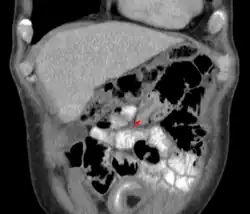

| An intussusception as seen on CT | |

An intussusception is often suspected based on history and physical exam, including observation of Dance's sign. A digital rectal examination is particularly helpful in children, as part of the intussusceptum may be felt by the finger. A definite diagnosis often requires confirmation by diagnostic imaging modalities. Ultrasound is the imaging modality of choice for diagnosis and exclusion of intussusception, due to its high accuracy and lack of radiation. The appearance of target sign (also called "doughnut sign" on a sonograph, usually around 3 cm in diameter, confirms the diagnosis. The image seen on transverse sonography or computed tomography is that of a doughnut shape, created by the hyperechoic central core of bowel and mesentery surrounded by the hypoechoic outer edematous bowel.[10] In longitudinal imaging, intussusception resembles a sandwich.[10] It is also called "pseudokidney" sign because hyperechoic tubular centre is covered by a hypoechoic rim producing a kidney-like appearance.[11]